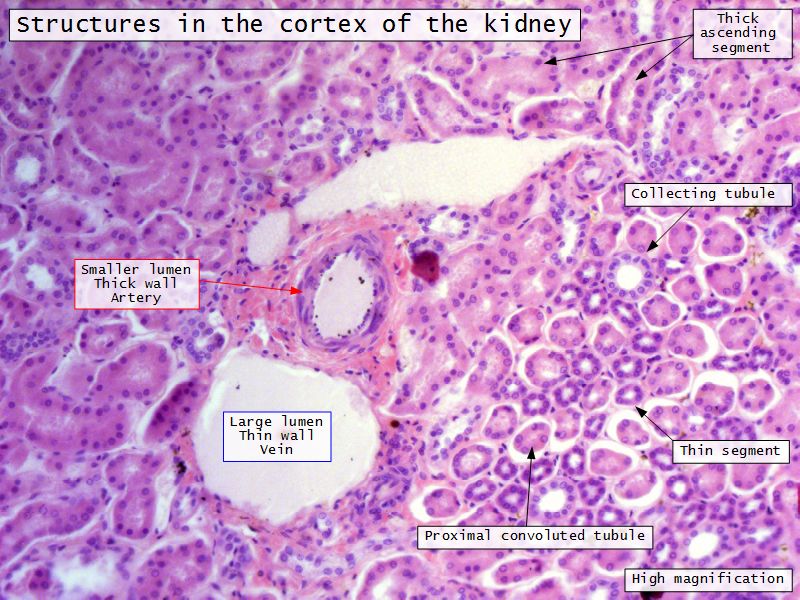

Appearance

- Cortex

- Renal corpuscles

- Convoluted tubules

- Medulla

- Loops of Henle

- Collecting tubules

Proximal convoluted segment

- Longest part of nephron

- Wide triangular cell

- Spherical nucleus

- Indistinct cell borders

- Luminal surface

- Striated brush border

Loop of Henle - thin

- Narrow lumen

- Thin wall

- Squamous epithelium

- Looks like capillaries

Collecting tubule

- Cuboidal to columnar epithelium

Main collecting ducts

- Wide lumen

- Pale staining columnar cells